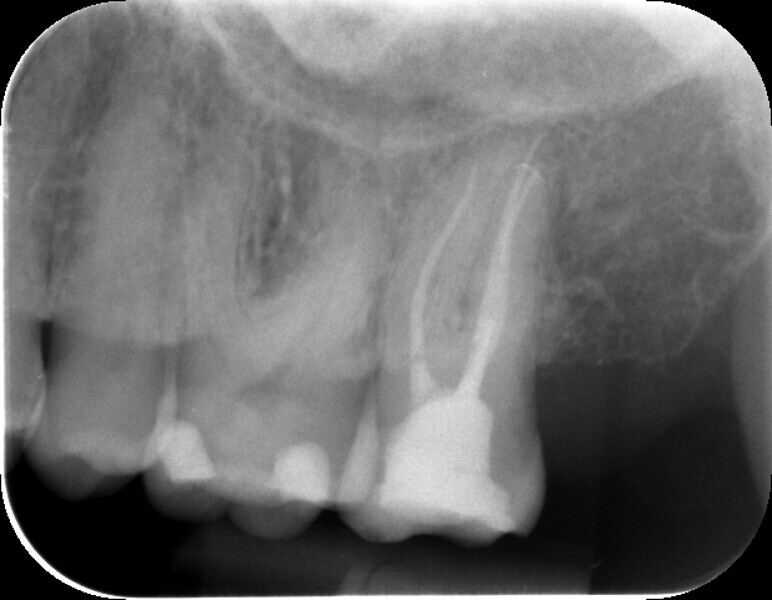

The mesiobuccal cusp tip served as a reference point for determining the working length of the mesiobuccal canal: preparation was performed over 19 mm up to size 30/.04 with the finishing file. Likewise, the distobuccal canal was instrumented to the same working length (reference point: distobuccal cusp tip). In comparison, the palatal canal had a working length of 21 mm; and here, too, the natural canal contour could be replicated with the compact OGSF sequence up to size 30/.04 with the finishing file.

HyFlex EDM master points of the same length were used for thermoplastic filling of the three root canals, and the canals were filled three-dimensionally with liquid gutta-percha. The AH Plus bioceramic sealer (Dentsply Sirona) provided the required sealing. Here, it is perfectly sufficient to coat only the lower part of the gutta-percha points with sealer. Furthermore, the canal entrances were covered with a flowable composite in Shade A1 in combination with a matching acid etching gel, primer and bonding agent. BRILLIANT EverGlow Flow high-performance composite (COLTENE) in the opaque version in Shade A3 was used for the final restoration. The final radiograph confirmed the reliable sealing of the three canals in tooth #27 (Fig. 7).